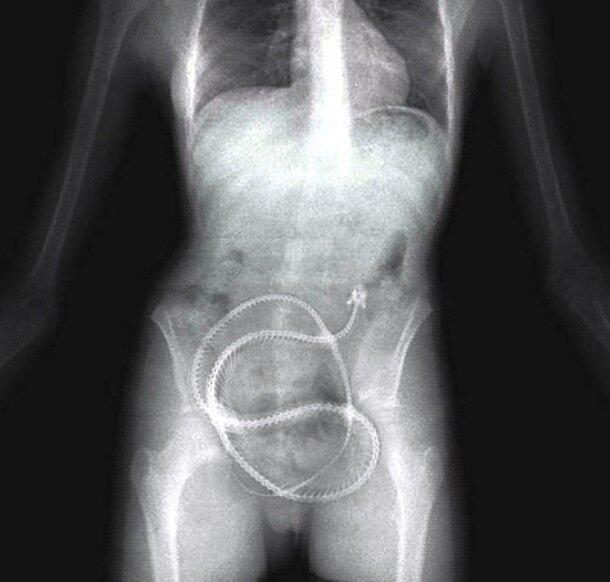

3. Столовые приборы.

В 2009 году, в Нидерландах, при обследовании 52-и летней женщины, которая поступила с жалобами на сильные боли в животе, хирурги с ужасом обнаружили на рентгеновском снимке 78 металлических фрагментов столовых приборов в ее желудке. Врачи незамедлительно начали операцию, по удалению инородных тел, пытаясь спасти жизнь женщины. Операция прошла успешно, и так же стало известно, что женщина страдала сильным психическим расстройством, из-за которого, каждый раз при приеме пищи, поедала еще и столовые приборы.